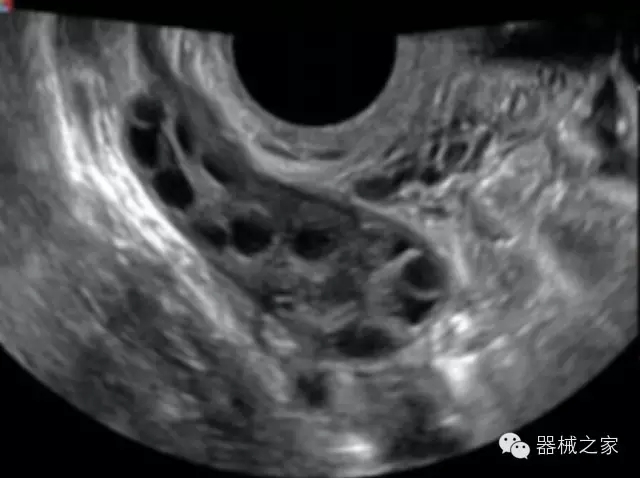

臨床圖片賞析

產(chǎn)品特點(diǎn)

·高效3D/4D成像技術(shù):高速的4D幀頻,豐富的3D成像模式,智能斷層切片功能;

POC領(lǐng)域解決方案

·外觀小巧;

·穿刺增強(qiáng)技術(shù):可有效提高進(jìn)針區(qū)圖像分辨率,提高進(jìn)針亮度,全面提高一次性穿刺的成功率;

全面的術(shù)中探頭解決方案

·小凸探頭:開放性手術(shù),實(shí)時(shí)監(jiān)測病灶位置,提高手術(shù)成功率,可應(yīng)用于麻醉科、肝膽外科、腫瘤外科、神經(jīng)外科、泌尿外科等手術(shù);

·L型線陣探頭:高分辨率圖像,清晰顯示病灶位置,提高手術(shù)成功率,可應(yīng)用于麻醉科、胸外科、肝膽外科、腫瘤外科、神經(jīng)外科、泌尿外科等應(yīng)用;

·MPTEE:經(jīng)食道探頭術(shù)中監(jiān)測,可測量心臟前負(fù)荷(左室舒張末期大小、右房大?。?、心排血量、后負(fù)荷、收縮功能、室壁運(yùn)動(dòng)分析、肝靜脈血流(與中心靜脈壓相關(guān))等,術(shù)后還能及時(shí)評估手術(shù)效果評估;

·獨(dú)有的大角度及實(shí)時(shí)溫控技術(shù),能同一切面顯示宮頸及宮體,有效減低了患者的痛苦,及保護(hù)粘膜保證了醫(yī)療安全;